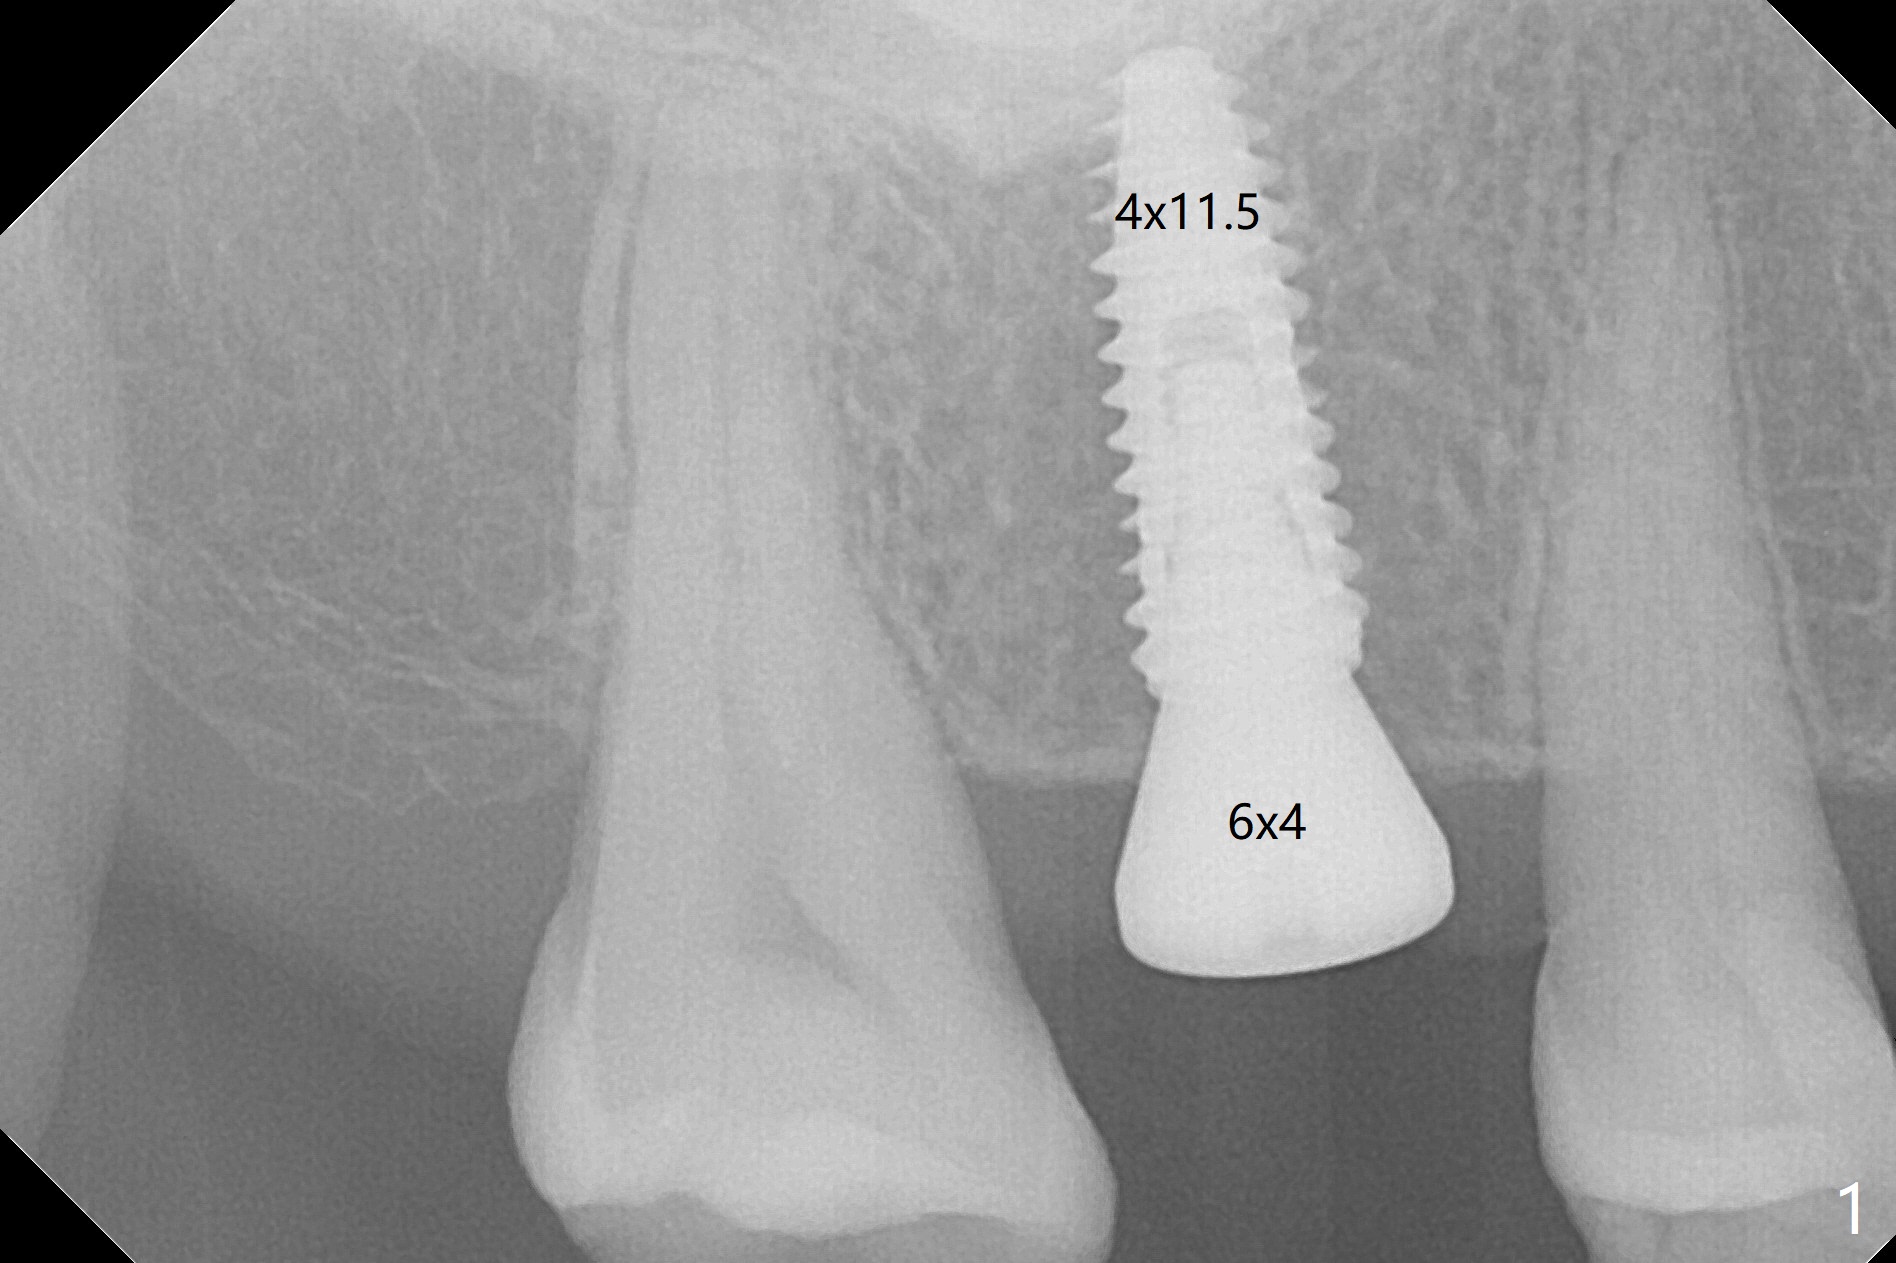

There is mild crestal bone loss 4.5 months postop (Fig.5).  When the patient returns for periodic exam and prophy 6 months post cementation, the crown is found to be loose, which is more likely associated with heavy mastication (long roots) and poor crown/implant ratio.  Since the distal contact is light, the case returns to lab.  PA taken following reseating the repaired abutment/crown shows crestal bone loss, which may be associated with the narrow ridge and/or the loose abutment.  The gingival cuff is less healthy (Fig.6).  The screw becomes loose again 4 months later.  When it is retightened, the distal proximal contact turns open (Fig.7 ^).  The crown appears to turn with the underlying abutment (Fig.8).  After breaking proximal contacts, the crown/abutment is retightened and pick up impression is taken.  It is likely that the abutment was not seated right when abutment-level impression was taken.  The crown table is slightly oversized (Fig.8). Three months later, the screw becomes loose for the 3rd time (unilateral mastication, pain at #19 without RCT).  The abutment hex is not worn.  The crown is removed and the abutment is reseated and torqued 30 Ncm.  Impression is taken for new crown.  The latter is cemented without removing the abutment (Fig.9 (note bone loss)).  In fact the crown/abutment should have been torqued with screw driver buried in place!